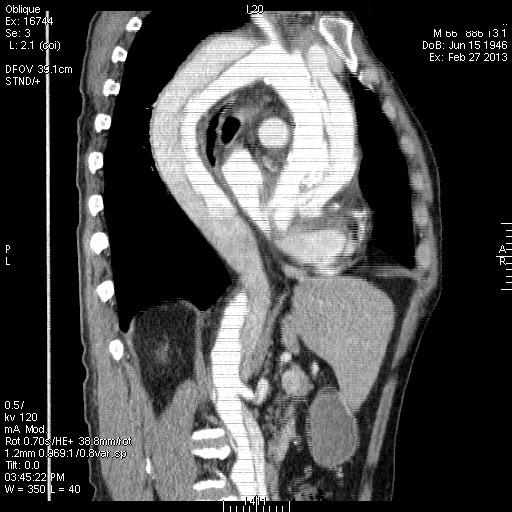

Расслаивающая аневризма аорты, Дебейки I

Пожилой пациент с жалобами на боли в грудной клетке. Болеет неделю.

Диссекция аорты

Диссекция аорты 1 типа по DeBakey , Стенфорд А .